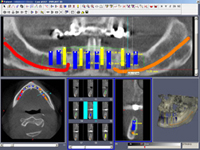

• Dokonalé vyšetření, stanovení diagnózy,naplánování ošetření - způsob, časový průběh,cena

Zavedení implantátů do kosti je většinou ambulantní chirurgický výkon, srovnatelný s vytržením zubu a většinou se provádí v lokální anestézii. Ve výjimečných případech je možné použít i analgosedaci či celkovou narkózu. Operaci provádí zubní lékař-implantolog při dodržení všech podmínek sterility pro operaci. Nástroje pro tuto operaci jsou konstruovány tak, aby výkon byl šetrný vůči kosti a zavedení implantátu bylo provedeno ve velmi krátké době. Díky kvalitní anestézii je výkon nebolestivý. Aby byl pooperační otok co nejmenší, je potřeba operovanou oblast chladit, dle poučení ošetřujícího lékaře. Lékař také ordinuje podle potřeby léky na bolest, případně antibiotika.

Průměrná doba hojení implantátů před provedením definitivního protetického ošetření je 3-4 měsíce, v případech, kde je nutné doplnit chybějící kost (různé metody, postupy a materiály) – tzv. augmentace) se může doba hojení prodloužit na 8-12 měsíců. S tím je pacient vždy předem seznámen svým lékařem.